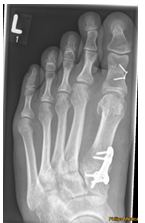

Begradigung durch Knochenverschiebung

Hierbei wird der Mittelfußknochen nach außen verschoben und mit zwei kleinen Schräubchen wieder befestigt (Osteotomie nach Chevron). Ebenfalls wird ein verkürzter Muskel gelöst, damit der Zeh in gerader Position verbleibt (sog. laterales Release). Sollte die Fehlstellung auch innerhalb der Zehe vorliegen, wird auch ein kleiner Keil am Großzehengrundglied entnommen (Osteotomie nach Akin).

Die Patienten können nach der Operation in einem Spezialschuh ohne Stützen voll belasten. Der Vorfußentlastungsschuh sollte bis zur Röntgenkontrolle für 6 Wochen getragen werden. Anschließend ist normales Gehen im Normalschuh möglich. Eine Thromboseprophylaxe ist für 5-10 Tage notwendig.